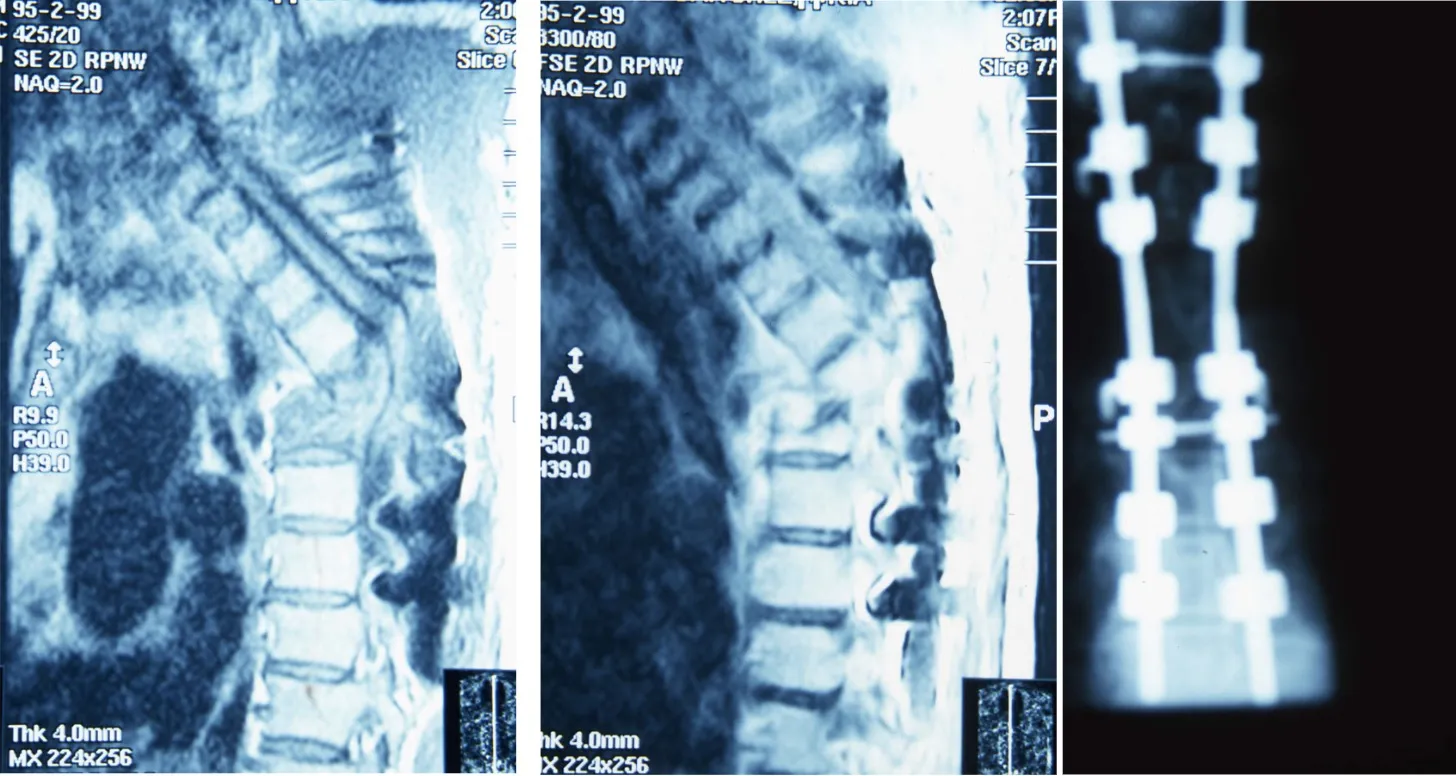

Tuberculosis vertebral

La infección por Mycobacterium tuberculosis, históricamente conocida como enfermedad de Pott, representa una forma particular de espondilodiscitis. Aunque su incidencia ha disminuido significativamente en países desarrollados, continúa siendo relevante en determinadas poblaciones. La tuberculosis vertebral se caracteriza por ser una enfermedad de evolución insidiosa que puede progresar de forma silente durante meses o años, manifestándose únicamente cuando se produce un colapso vertebral que genera una lesión neurológica grave.

- Colapso vertebral: la destrucción del disco y de los cuerpos vertebrales puede conducir a un colapso de las vértebras afectadas. Este fenómeno genera una cifosis, es decir, la columna se vence hacia adelante en la zona afectada, alterando significativamente la biomecánica vertebral.

- Inestabilidad vertebral: la pérdida de la integridad estructural de la columna genera una inestabilidad segmentaria que puede comprometer la protección de la médula espinal y las raíces nerviosas.

- Riesgo neurológico: el colapso vertebral, junto con la formación de abscesos epidurales y la inflamación local, pueden comprimir la médula espinal o las raíces nerviosas, generando lesiones neurológicas potencialmente graves e irreversibles si no se tratan a tiempo.

Técnicas quirúrgicas y resultados

- Desbridamiento y fusión posterior: acceso por la parte posterior de la columna con limpieza del foco y estabilización mediante tornillos pediculares. Resultados exitosos en el 97% de los casos.

- Abordaje y fusión anterior: acceso directo al foco infeccioso por delante, permitiendo una limpieza exhaustiva y colocación de injerto o caja intersomática. Resultados exitosos en 82-100% de los casos.